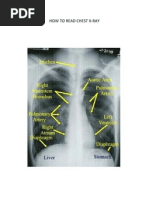

HOW TO INTERPRET A CHEST X-RAY

THE TEN-POINT CHECKLIST

1. AP or PA X-ray view

2. Depth of inspiration

3. Rotation

4. Cardiothoracic ratio- should be less than 50%

on a PA view

5. Both domes of diaphragm should be clearly

seen and well defined

6. Heart borders- clearly seen and well defined

7. Hila- density, position and size- The left hilum

should be at the same level or higher than the

rights. Never lower. The hilar density on each

side should be similar.

8. Bones- should be normal

9. Hidden areas - lung apex, superimposed over

the heart, around each hilum, below the

diaphragm.

10. Clinically correlate